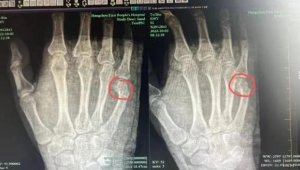

- 辅导作业一道题讲了半小时,杭州爸爸锤桌锤到骨折…(图)